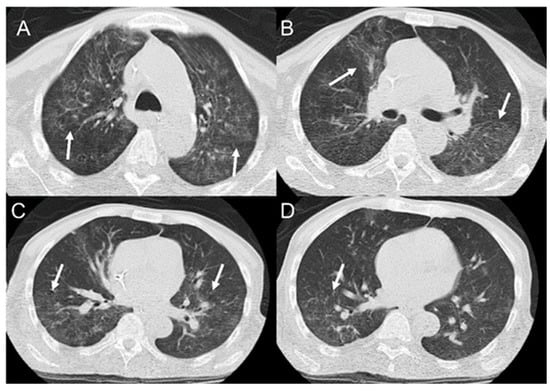

- Rosa Junior, M.; Baldon, I.V.; Amorim, A.F.C.; Fonseca, A.P.A.; Volpato, R.; Lourenco, R.B.; Baptista, R.M.; de Mello, R.A.F.; Pecanha, P.; Falqueto, A. Imaging paracoccidioidomycosis: A pictorial review from head to toe. Eur. J. Radiol. 2018, 103, 147–162. [Google Scholar] [CrossRef]

- Queiroz-Telles, F.V.; Pecanha Pietrobom, P.M.; Rosa Junior, M.; Baptista, R.M.; Pecanha, P.M. New Insights on Pulmonary Paracoccidioidomycosis. Semin. Respir. Crit. Care Med. 2020, 41, 53–68. [Google Scholar] [CrossRef]

- Queiroz-Telles, F.; Escuissato, D.L. Pulmonary paracoccidioidomycosis. Semin. Respir. Crit. Care Med. 2011, 32, 764–774. [Google Scholar] [CrossRef]